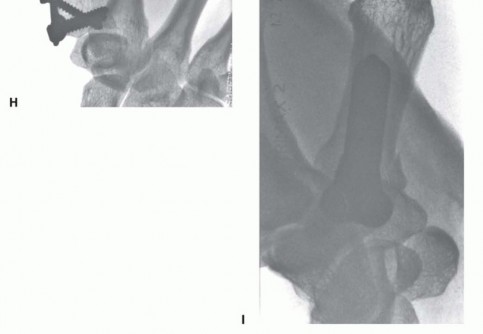

In cases of severe, non-reconstructable articular comminution where internal fixation is impossible, joint-spanning external fixation combined with limited internal fixation (K-wires) is utilized. The external fixator relies on the principle of ligamentotaxis to restore length and align the articular fragments. Pins are placed in the trapezium (or radius) and the thumb metacarpal shaft, distracting the joint to allow for secondary bone healing while preventing collapse.

Image